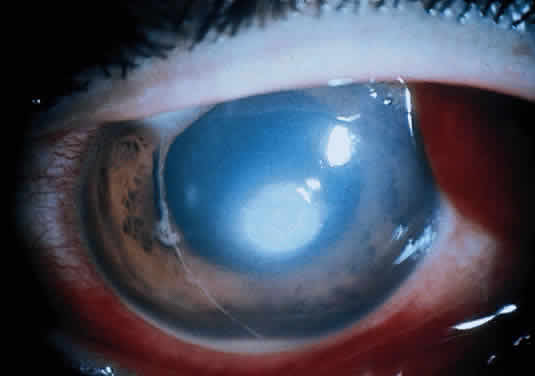

Corneal ulcers caused by S. pneumoniae are typically described as serpiginous or creeping and most often spread toward the center of the cornea. They are characterized by a gray-yellow disc-shaped ulcer with an overhanging margin at the advancing edge (Fig. 5). The ulcer usually progresses rapidly, extending into the deep stroma and often leading to corneal perforation. Extensive damage to corneal tissue, as well as a characteristic sterile hypopyon, are caused by the rapid production of bacterial exotoxin within the stroma.40,41